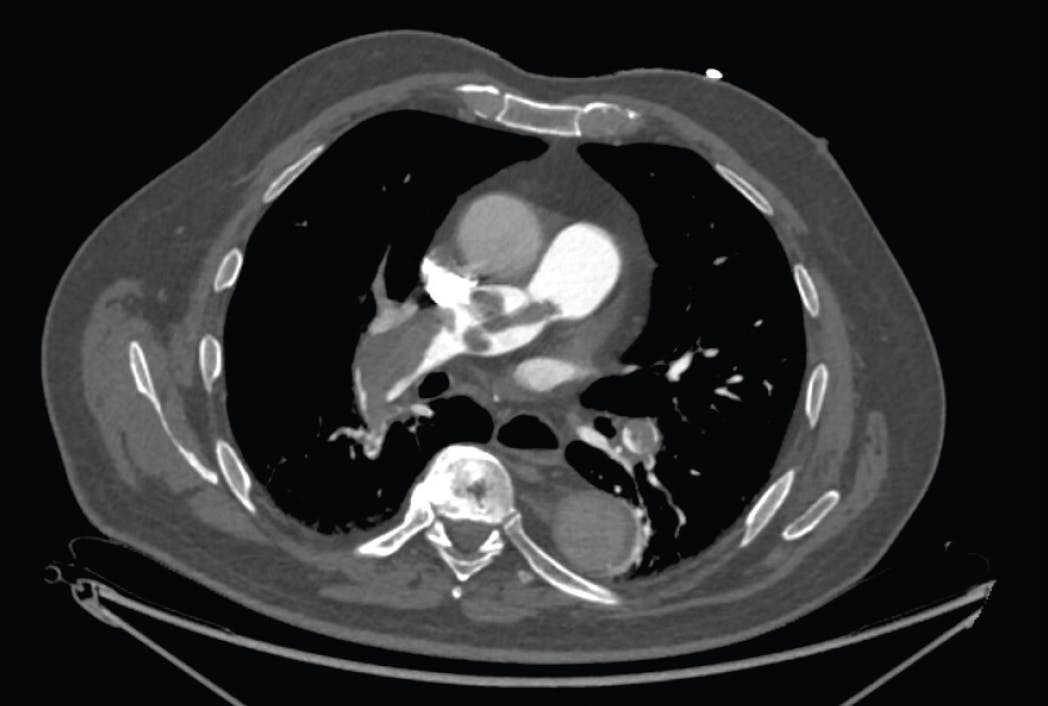

The most common presenting features of PE include dyspnea and pleuritic chest pain, while less common symptoms include cough, hemoptysis, dizziness, and syncope.3 Initial evaluation generally includes an assessment of hemodynamic status and oxygenation. The electrocardiogram usually demonstrates sinus tachycardia, although arrhythmias and patterns of right ventricular (RV) strain may be present. Laboratory testing usually demonstrates an elevated D-dimer; biomarkers, including troponin levels and B-type natriuretic peptide (BNP), may or may not be elevated depending on the degree of RV strain, and lactic acid levels may further indicate the extent of end-organ ischemia. When the diagnosis is equivocal, an echocardiogram may be performed. The distinct echocardiographic pattern, with akinesia of the RV free wall and sparing of the RV apex, was first described by McConnell et al.4 When the clinical suspicion is high, CTA of the pulmonary arteries (PAs) is considered gold standard for confirming or ruling out the diagnosis of PE but also defining the extent and distribution of thrombus within the pulmonary arterial tree (Figure 1).3

Figure 1. Large saddle PE with extensive involvement of the right interlobar PA. Left PA not pictured in this axial slice.